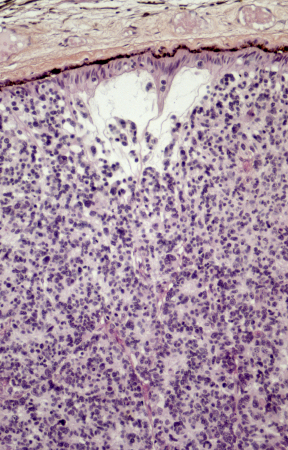

[Figure caption and citation for the preceding image starts]: Histopathology of retinoblastoma. This image demonstrates the classical features of retinoblastoma, including densely packed, small, round tumor cells with hyperchromatic nuclei and scant cytoplasm, arranged in sheets. The absence of Flexner-Wintersteiner rosettes in this specimen does not preclude the diagnosis, as their presence is not obligatory. These histopathological features are typical of this aggressive retinal tumor and provide critical information for diagnosis, staging, and prognosisPR J. L. Kemeny, ISM/Science Photo Library; used with permission [Citation ends].

[Figure caption and citation for the preceding image starts]: Light micrograph of a retinal section from a patient with retinoblastoma, a rare form of intraocular cancer. The tumor shows disrupted retinal architecture and infiltrative growth of atypical cells. Immunohistochemistry with anti-rhodopsin antibodies highlights areas of preserved photoreceptor differentiation within the retinal tissue. This staining aids in identifying residual retinal layers amidst the malignant cellular proliferationPR J. L. Kemeny, ISM/Science Photo Library; used with permission [Citation ends].